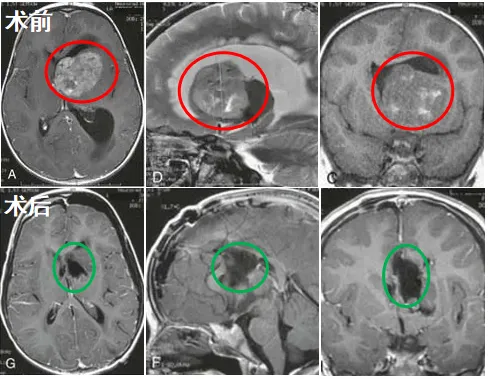

当我在医院看到我的女儿瑟琳娜时,她依然躺在病床上,人事不省。医生拿着核磁走向我,指着片子上显而易见的巨大侧脑室肿瘤对我说:“你女儿情况不妙。”我下意识地追问,医生告诉我:“脑积水已经将孩子的大脑撑到变形,而且这个肿瘤也严重威胁到了她的生命,必须紧急抢救,不然来不及了!”

情况危急,巴教授向我解释了这场手术的具体规划:他们将先通过脑室外引流术缓解致命的脑积水,随后在精密神经导航的辅助下,为瑟琳娜实施高难度的肿瘤切除手术。

在我同意后,女儿被推入手术室。经过数小时的煎熬等待,走出手术室的巴教授笑着告诉我,肿瘤得到全切,手术十分成功。我紧绷的情绪再也克制不住,瞬间泪流满面。我可爱的女儿瑟琳娜,她得救了。

尽管女儿的肿瘤属于高级别的间变性室管膜瘤,以后还需要放化疗,但是我知道,这一次的难关我们成功闯过来了,也为后续的辅助治疗提供良好的基础!